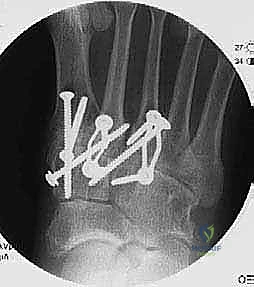

Second and Third TMT Joints Definitive Stabilization:

- "Now, let's move to the second metatarsal. We'll use our cannulated system here. Drill over the guide pin with the appropriate cannulated drill bit for our 3.0-mm cannulated screw. Remember to protect the tibialis anterior tendon during this entire process."

- "Once the pilot hole is drilled, measure your screw length. The bone of the cuneiforms can be softer, so be prepared to use a washer under the screw head if needed to prevent pull-through. Insert the 3.0-mm cannulated lag screw, achieving good compression."

- "Repeat this similar technique for the third metatarsal. Drill over the guide pin with the cannulated drill, measure, and insert the 3.0-mm cannulated lag screw from the third metatarsal into the lateral cuneiform."

- "To further enhance stability and compression, we will now place compression staples. For the third TMT joint, we'll place a compression staple dorsally, spanning the fusion site."

* "And for the second TMT joint, another compression staple dorsally, spanning the fusion site between the second metatarsal and the intermediate cuneiform. This adds robust, broad-surface compression, particularly helpful in the midfoot."